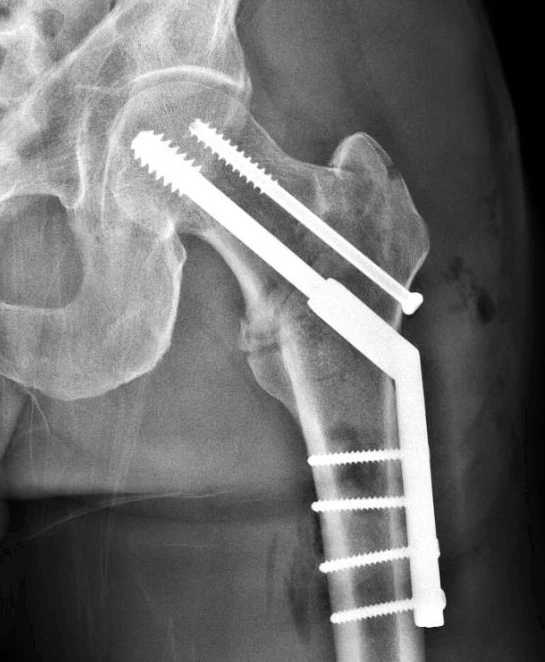

Honestly, I think the lack of speed and abruptness of the fall was the reason it broke. It’s not like I hit my hip on the road. The bone is way deep in my upper thigh. It is that my lower leg hit the ground and leveraged that force on my bone and it broke above the femur. The speed I hit the pavement, because of the lack of fiction from water, really added to the whole outcome. The same as the first week in the Tour, lots of crashes and broken things because of water.

It is Interesting how you described exactly what caused your femur to break at the trochanter. I broke my femur in the exact same spot three years ago, and the memory of the fall is very fuzzy, but I thought it was because I landed square on my hip on the pavement. Maybe I did the same thing as you - hit in the lower leg first, leveraging upward to the head of the femur. Glad you are healing correctly. It was about this time in my recovery when I realized I was screwed - they put the femur back together wrong, my leg was shorter by 3/4", and it took two surgeries and 18 months to get back to normal.

Yeah-Obviously bone density and strength has a lot to do with whether you fracture something in a fall or not. That being said, I have a ton of pictures from guys in the upper 20’s and 30’s who did the exact same thing as me. I have to assume I’m more fragile than I was younger. But, my doctor, a trauma surgeon at the University of Iowa, said that my bone was super hard when he drilled into it. Said something like I must of fallen pretty hard to break it. I doubt he just said it to make me feel better, but there is always that chance I guess. I think my bike going out from under me so quickly and me hitting the bricks at not a slight angle, like it would be if I were going faster, but acutely, made a huge difference. Plus, the bricks weren’t super wet, so I sort of stuck when I hit. All these things factor in to the resulting broken hip. Like I put in my post, I am so surprised about how many broken hips and femurs are out there. There are 3 or 4 more incidences listed on my Facebook page. Weird. https://www.facebook.com/steve.tilford.73